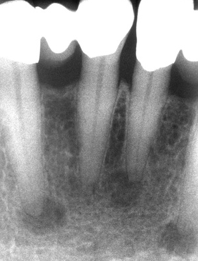

periapical cemento-osseous dysplasia

focal cemento-osseous dysplasia